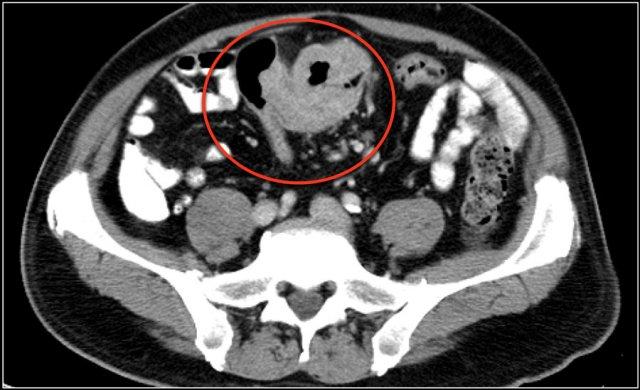

Các hình ảnh này thuộc về bệnh nhân bị tắc ruột non dạng quai kín.

Lưu ý nhóm các quai ruột non có thành dày ở vùng bụng trên phải (mũi tên vàng).

Phù nề mạc treo ruột (mũi tên đỏ) cho thấy tình trạng tăng áp lực tĩnh mạch do thắt nghẹt.

Giãn mạch máu

Tăng áp lực tĩnh mạch trong thắt nghẹt cũng dẫn đến giãn tĩnh mạch (mũi tên vàng).

Bệnh nhân này cũng có tắc ruột dạng quai kín với kiểu ngấm thuốc xám của các quai ruột bị thắt nghẹt (mũi tên đỏ).

Lưu ý sự ngấm thuốc bình thường của ruột non ở phía trên vị trí tắc nghẽn (mũi tên xanh lá).